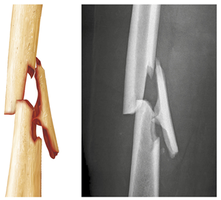

Fracture Classification

Position: Nondisplaced (normal alignment) vs. displaced (misaligned).

Completeness: Complete (all the way through) vs. incomplete.

Skin penetration: Open (compound) vs. closed (simple).

Four stages: hematoma formation, fibrocartilaginous callus formation, bony callus formation, bone remodeling.